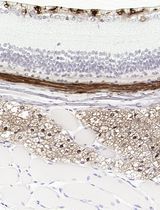

Fluoro-Jade is a fluorescent derivative used for histological staining of degenerating neurons. This technique is simple and sensitive enough to label distal dendrites, axons, axon terminals as well as neuronal bodies. Fluoro-Jade has excitation and emission peak of 480 and 525 nanometer respectively. It can be visualized using a fluorescein/FITC filter. Some reports have demonstrated that Fluoro-Jade can also be useful to detect glial cell death (Anderson et al., 2013; Damjanac et al., 2007).